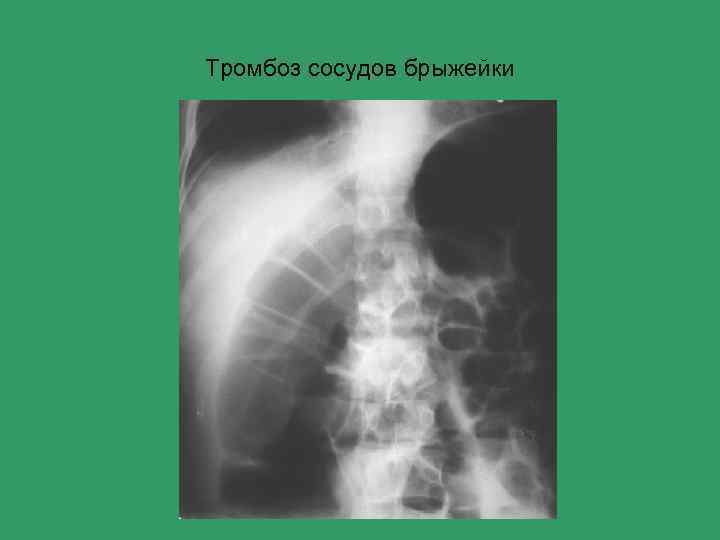

Острый живот Основные причины 1) Перфорация полого органа 2) Кишечная непроходимость 3) Острый аппендицит 4) Жёлчекаменная болезнь 5) Острый панкреатит 6) Абсцесс брюшной полости 7) Почечная колика

Алгоритм лучевого обследования при синдроме острого живота • Уровень I Обзорная рентгенограмма живота, УЗИ Картина ясна • Картина не ясна Латерограмма • Уровень. II Рентгеноконтрастное исследование, КТ

Тромбоз сосудов брыжейки